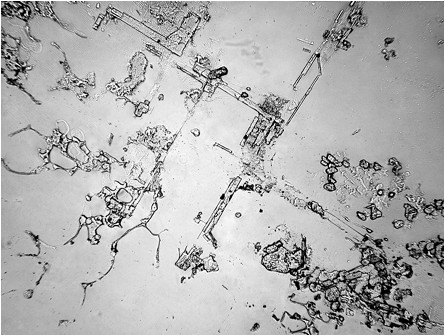

Dacă, pe aceste tipuri diferite de lacrimi, dar și pe altele, punem microscopul, la propriu, vom putea observa lucruri total surprinzătoare.

Cercetătorii Institutului de Oftalmologie din Madrid au analizat la microscop textura diferitelor lacrimi, iar rezultatul a fost unul neașteptat.

Compoziția lor poate părea asemănătoare sau chiar identică, uneori. Singura diferență constatată de noi, adesea, este gustul lacrimilor care pote fi, uneori, mai sărat, însă o imagine detaliată ne demonstrează că, în realitate, nu este deloc așa.

Fiecare categorie este diferită de cealaltă, iar compoziția lor diferă în funcție de sentimentele noastre.

Diferența o fac sentimentele exprimate prin intermediul lacrimilor, sunt de părere cercetătorii.

În funcție de situația în care se află sistemul neuroendocrin, în lacrimi se secretă diferite tipuri de hormoni și neurotransmițători, de a căror cantitate și tipologie depinde compoziția moleculară a lacrimilor înainte ca acestea să apară în exterior.